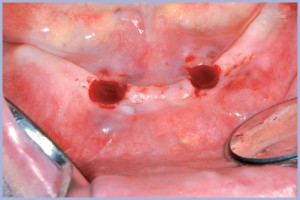

Verificata la quantità di osso disponibile con esame TC (Fig. 1) vengono posizionati con tecnica flapless minimamente invasiva 2 impianti di diametro 4,1 mm, lunghezza 10 mm (Figg. 2-4).

- Fig. 2 – Preparazione dei siti con tecnica flapless

- Figg. 3 , 4 – Impianti Exacone® 4,1 x 10 mm inseriti, tecnica bifasica

- Fig. 4